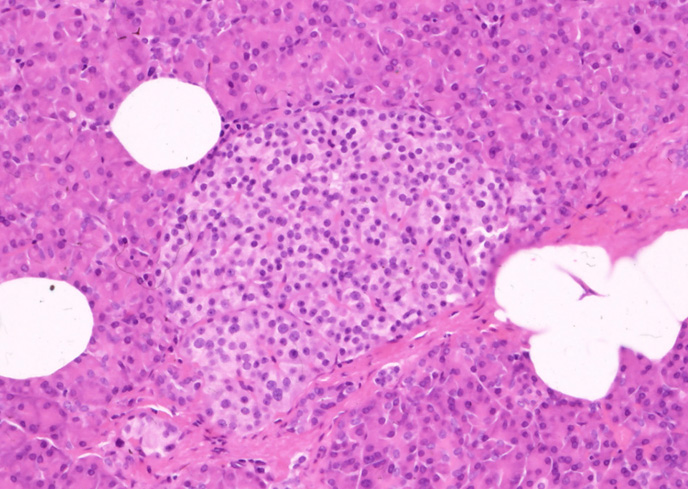

血液グルコース濃度を調節するホルモンを分泌する器官でランゲルハンス島 islets of Langerhansと呼ばれる細胞集団をつくり, 膵臓全体に見られるが尾部に多い。サイズは大小さまざまで, 数個から何百個の細胞から構成され, 総体積は膵重量の1-2%。多角形の細胞が短く不整なコード状構造を示し,窓の開いた毛細血管網が間質となる。膵ランゲルハンス島の内分泌細胞は胎生9-12週に確認されるようになる。。*1

←クリックで大きな画像が見られます。ランゲルハンス島のHE染色像

HE像でも小さめな細胞が辺縁に認められ、おそらくGlucagon産生のA細胞と考えられる。